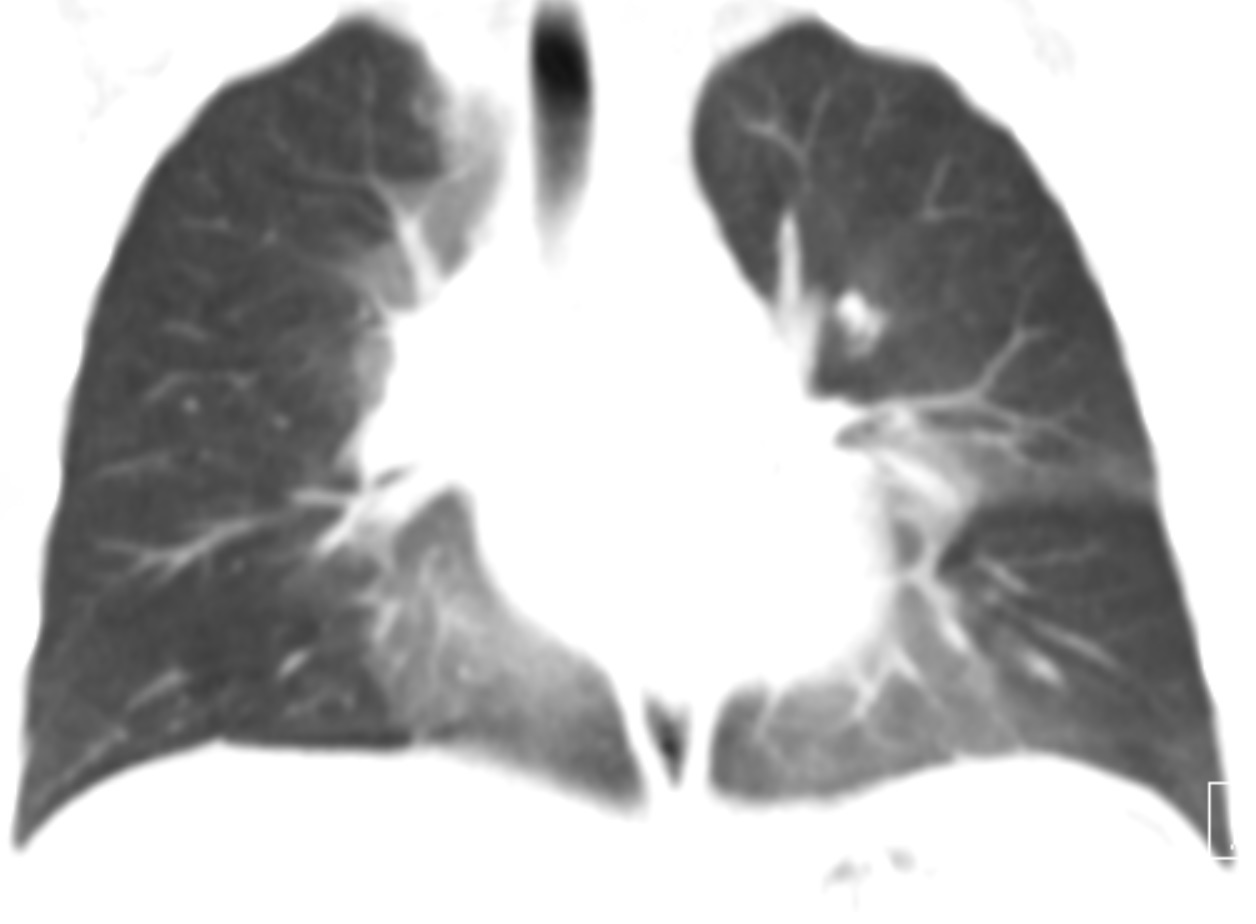

premature baby w/diffuse GGO, lack of pleural fluid and low lung volumes

RDS/Surfactant deficiency disease

TTN, neonatal PNA, and meconium aspiration tend to have hyperinflated lungs